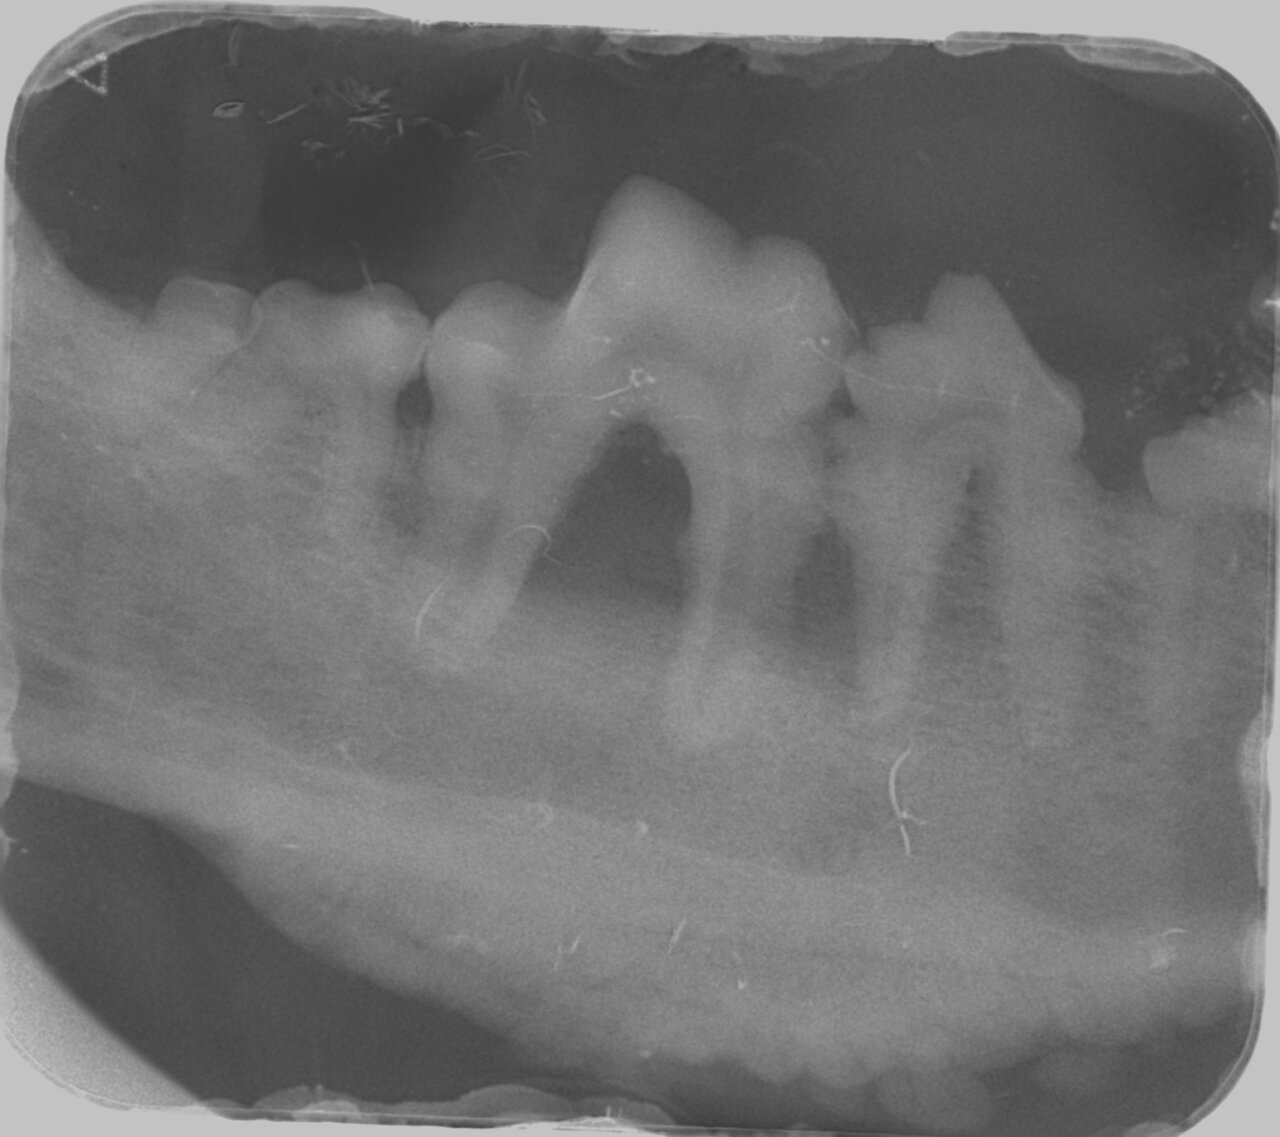

Para el diagnóstico de la EP, además de realizar un examen periodontal a través del sondaje debemos apoyarnos en la radiografía, ya que nos proporciona información acerca de la cantidad de pérdida ósea existente, así como del patrón que sigue esta pérdida (horizontal y/o vertical). En dientes multirradiculares, podemos servirnos de la furca para evaluar la pérdida de hueso, ya que aparecen áreas radiolúcidas bajo la bifurcación radicular a medida que se produce la destrucción ósea.

De acuerdo a esta pérdida del hueso alveolar detectada a nivel radiológico, clasificaremos la EP en cuatro grados:

- Grado 3 (PD3): pérdida del soporte óseo de un 25-50 % (imagen 8).

- Grado 4 (PD4): pérdida del soporte óseo mayor de un 50 % (imagen 9).

Además de permitirnos evaluar el grado de enfermedad periodontal, también hace posible seleccionar el mejor tratamiento en función de su patología y las posibles complicaciones, como las fracturas mandibulares iatrogénicas en perros de talla pequeña con enfermedad periodontal PD4 (imágenes 10 y 11).